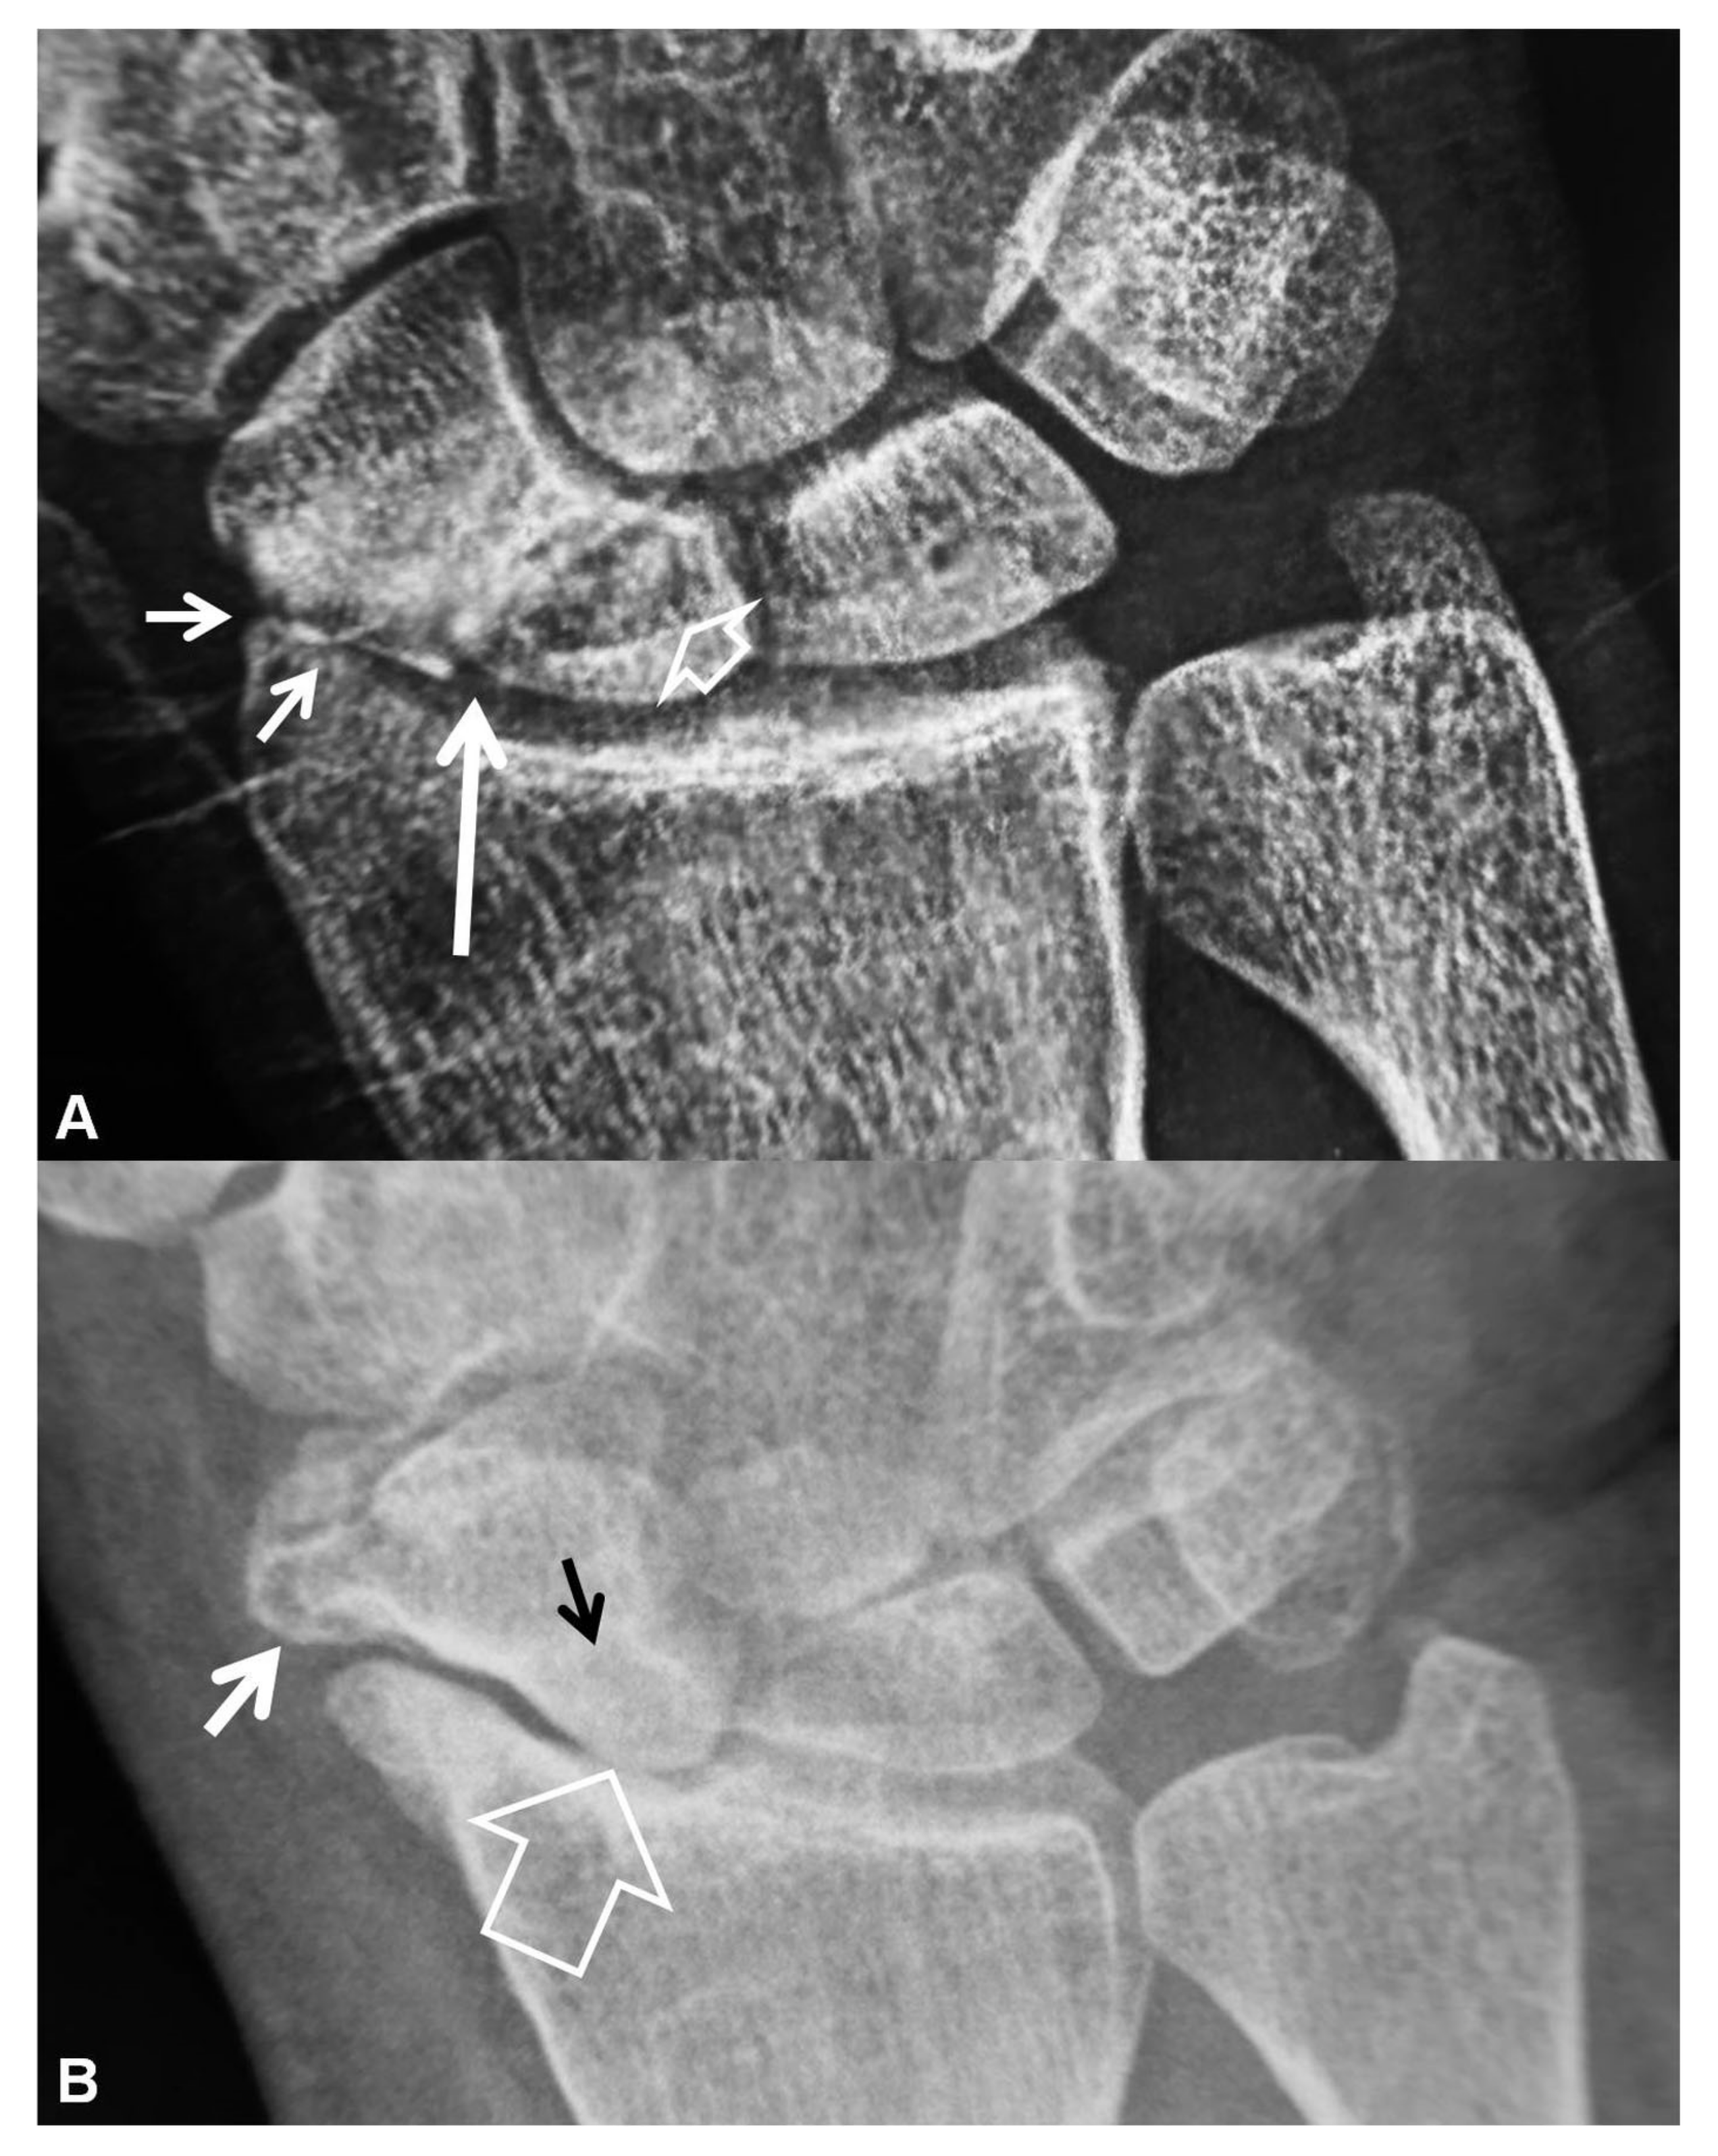

Figure 3.

PA radiographs. (A) A 35-year-old male patient with a history of wrist pain for 10 years. Scaphoid fracture non-union (arrow), proximal pole cyst formation (open arrow) and radial side joint space narrowing (short arrows) are diagnostic of stage I SNAC wrist. (B) A 44-year-old male patient known scaphoid osteonecrosis. Proximal pole osteonecrosis (black arrow) combined with radioscaphoid space narrowing (open arrow) and osteophytosis of the scaphoid bone (short white arrow) are diagnostic of a SNAC wrist. The proximal carpal arc is disrupted and the capitate bone is proximally migrated.